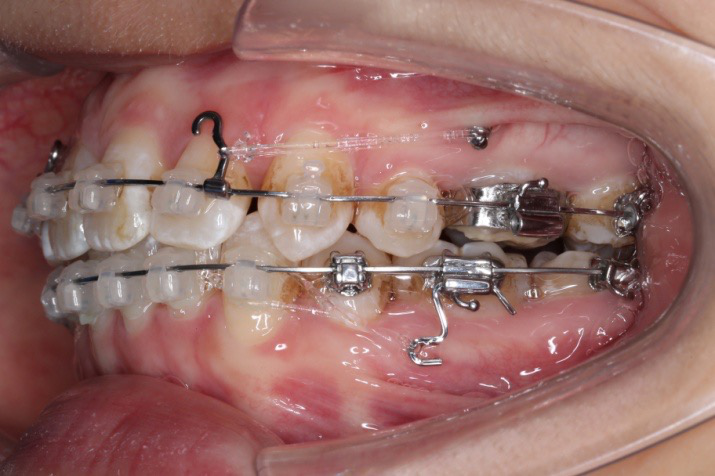

2018.03.01上TPA加17、27颚侧牵引钩,压低17、27颚尖下颌43、32重粘,下颌0.016*25niti

2018.04.20  间隙基本关闭,上颌重新整平,精调

2018.5.25  (19个月)拆TPA,16、26粘tube 上颌0.14*25cu-niti  下颌0.018*25niti2018.7.23  上颌 0.017*25TMA,下颌0.017*25ss43压低曲,双侧后牙垂直牵引

2018.09.29  15、43、16、17、11、21重粘,上0.016*25cu-niti 下0.018niti 上连扎